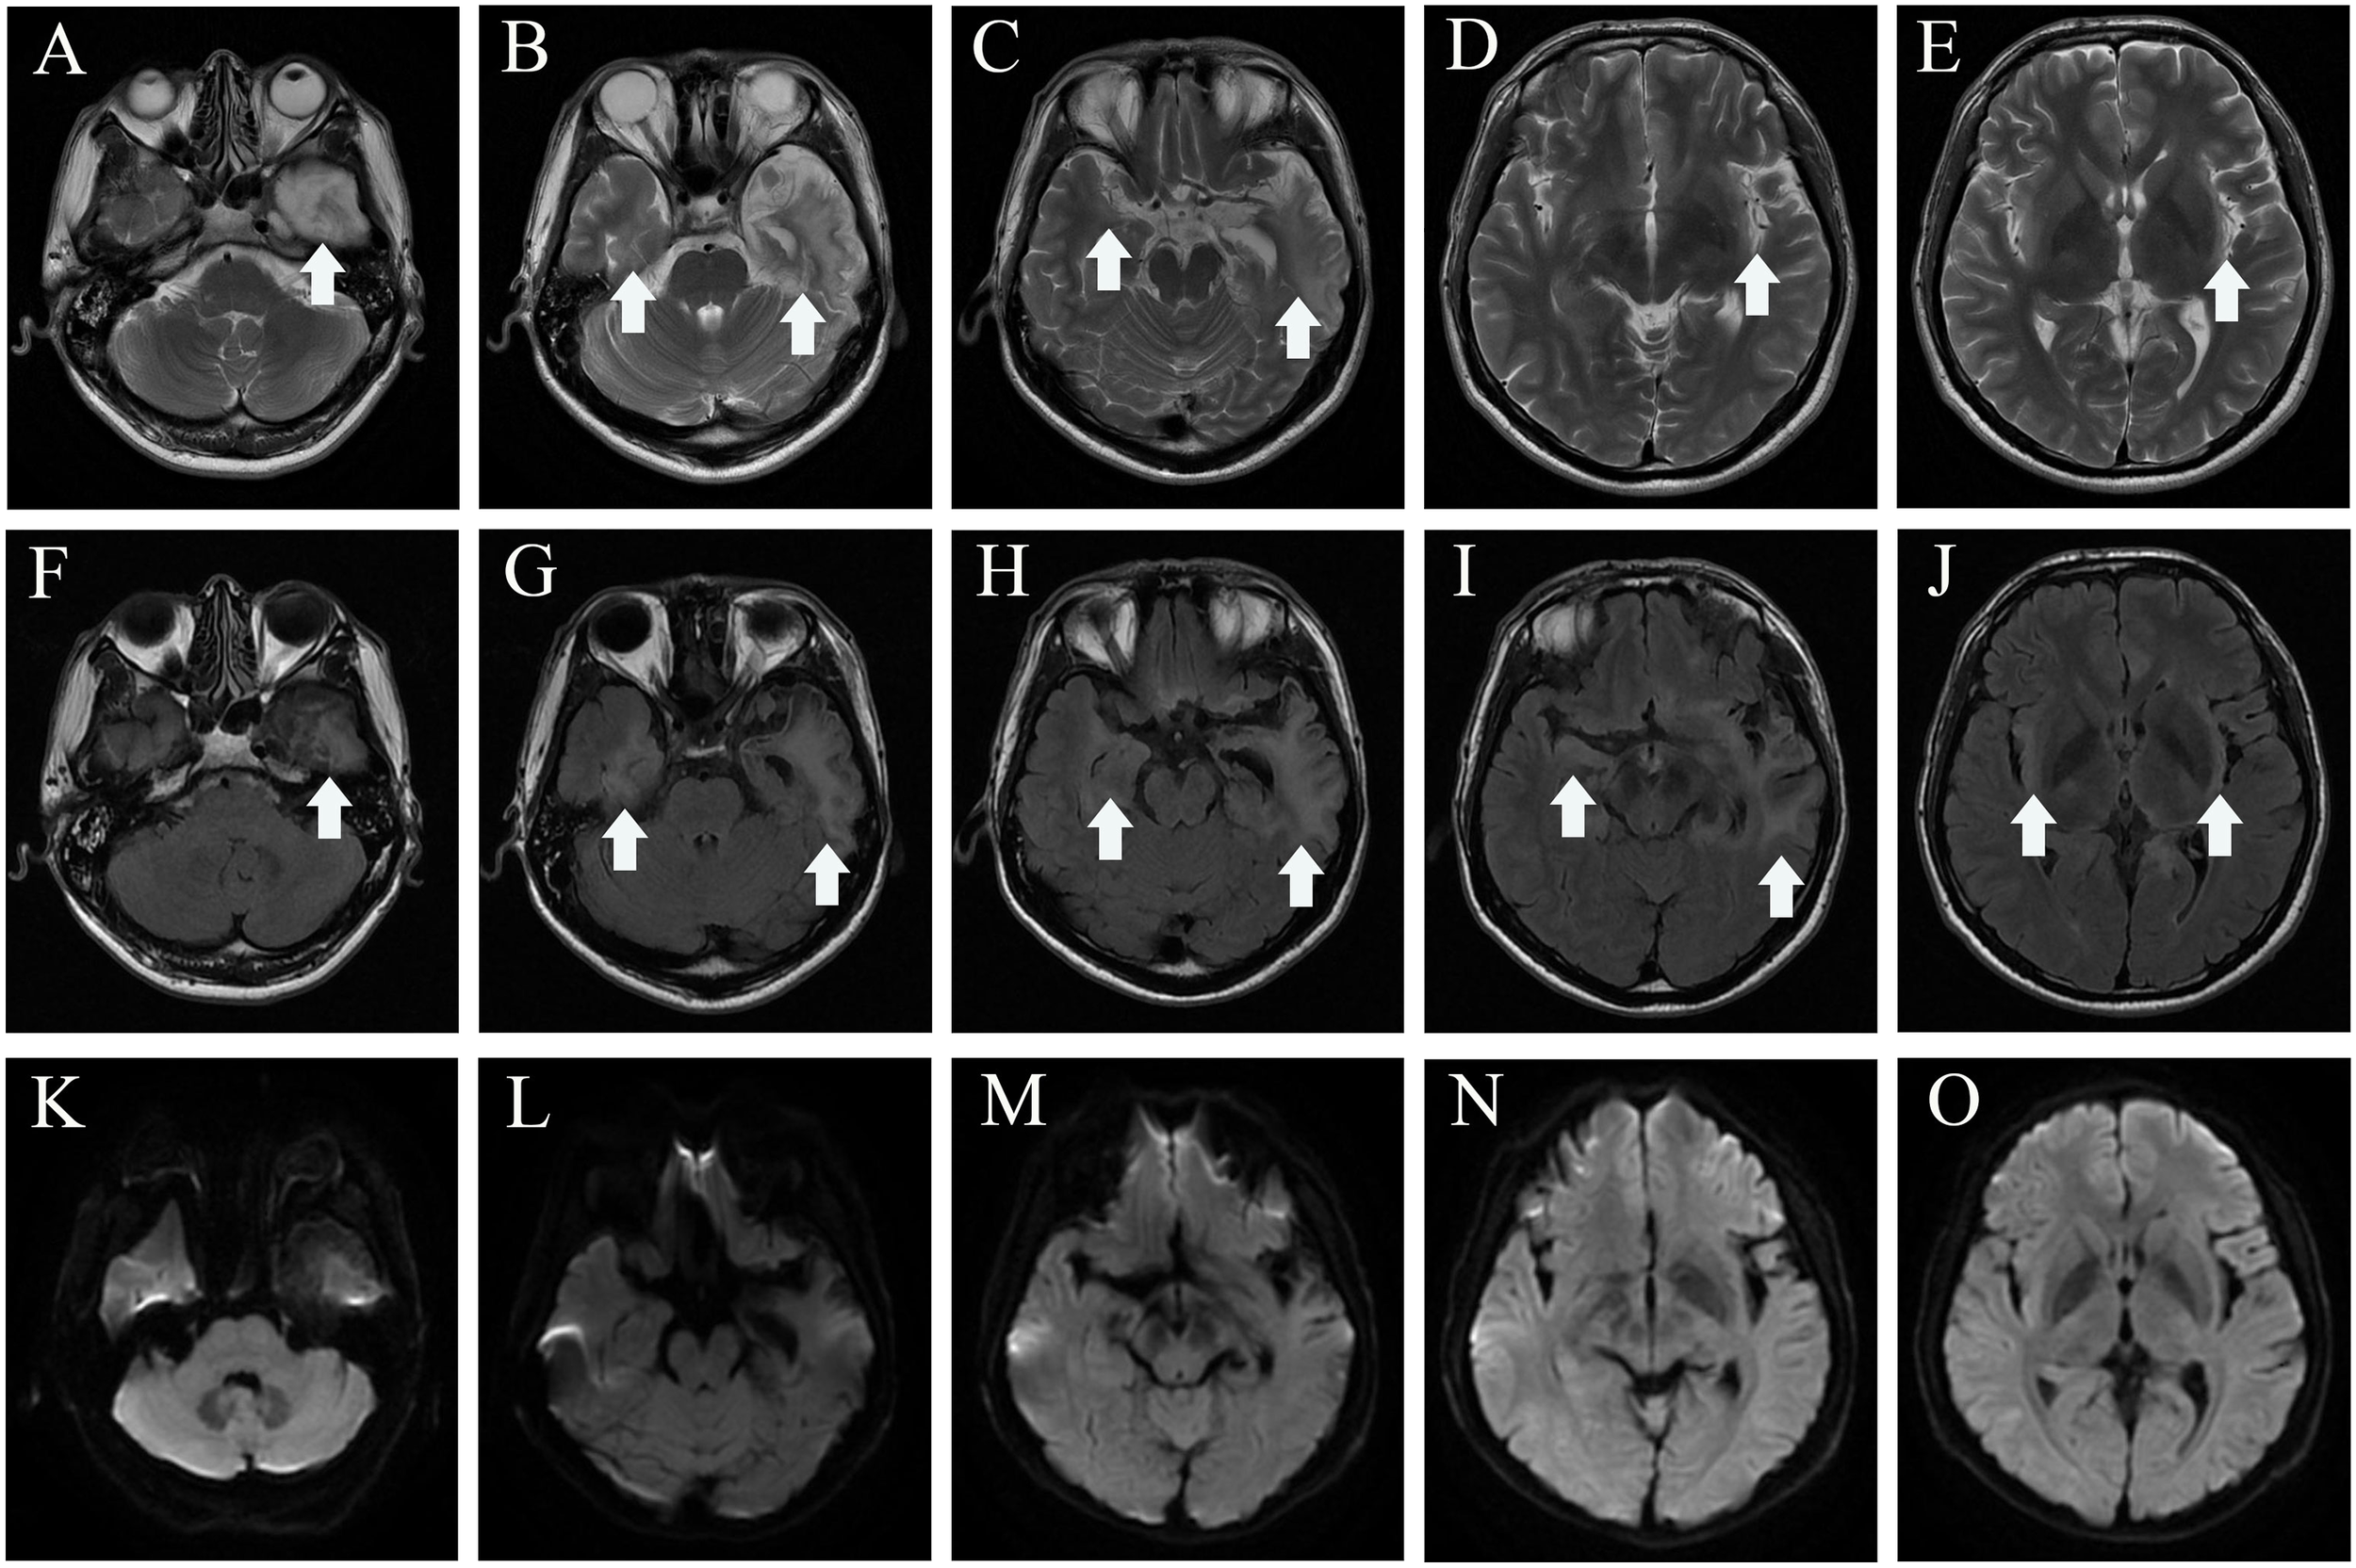

In mid-July 2022, a previously healthy 30-year-old man experienced acute headache, fever, somnolence for 4 days, and blurred consciousness for 1 day. Four days before admission to the local hospital, the patient had no evident cause of headache and fever. Meanwhile, the body temperature sustained a range of 39.0°C–39.5°C. He also had daily periods of irrepressible need to sleep, and his family-reported total 24-h sleep time was 16 h–18 h. After waking up, he could perform routine activities, such as washing and eating, and then continue to sleep quickly. The aforementioned symptoms were not relieved after using cold remedies (details are unknown). 2 days before admission, nausea with non-ejection vomiting, poor reaction, and blurred consciousness appeared. His sleepiness was worsening, and he could barely recognize his families. Serological tests for blood routine examination showed elevated leukocyte count: 17.15 × 109/L [normal range (NR) (4–10), × 109/L] and neutrophil count: 15.56 × 109/L [NR, (1.6–7.3) × 109/L]. Creatine kinase and creatine kinase isozyme was tested above 40,000 U/L (NR, 25.0 U/L–200.0 U/L) and 6,000 U/L (NR, <25.0 U/L), respectively. Analysis of cerebrospinal fluid (CSF) showed a slightly elevated protein level of 480 mg/L (NR, 80 mg/L–430 mg/L) and mild pleocytosis [white blood cell (WBC) count of 34 × 106/L [NR, (0–8) × 106/L]. The glucose level was normal, with high initial cranial pressure (290 mmH2O) and high final cranial pressure (200 mmH2O). Brain magnetic resonance imaging (MRI) revealed multiple lesions scattered in the left frontal lobe, bilateral temporal lobe, bilateral insula lobe, and hippocampus showing hyperintensity on T2-weighted and diffusion weighted imaging (DWI) (Figures 1A–J). Given anti-infection (cefoperazone sulbactam sodium), the body temperature still fluctuated above 39.0°C. Moreover, his families complained that the patient could not recognize them, had difficulty eating by himself, and experienced urinary incontinence, so he was referred to our hospital.

Figure 1

MRI before admission (A–J), axial T2-weighted image (A–E), and diffusion-weighted imaging (F–J) show a hyper intense signal in the left frontal lobe, temporal lobe, bilateral insula lobe, and hippocampus. MRI of after IVIG use (K–T), axial T2-weighted image (K–O), and diffusion-weighted imaging (P–T) show that the lesions scattered in the left frontal lobe, bilateral temporal lobe, bilateral insula lobe, and hippocampus were not significantly different from before. The white arrowhead showing lesions in MRI. MRI, magnetic resonance imaging.

The individual received a 10-day course of intravenous acyclovir sodium (10 mg/kg body weight administered three times daily for 10 consecutive days), in addition to high-dose intravenous methylprednisolone pulse therapy (500 mg/day for 2 days, followed by 1,000 mg/day for 3 days). His body temperature gradually appeared normal, but the level of consciousness remained drowsiness and the communication with others was even difficult because of impaired comprehension. The mRS score was still 5 (NR, 0). Then, a third CSF analysis was performed with normal cranial pressure, and the WBC count was 80 × 106/L [NR, (0–8) ×106/L] with 82% lymphocytes. Additionally, there was a notably increased protein level of 774.5 mg/L (NR, 80 mg/L–430 mg/L), whereas the glucose level remained within the normal range. Results of polymerase chain reaction (PCR) analysis were negative for HSV-1. AE auto-Abs such as anti-NMDAR, LGI1, and AMPAR were screened by cell-based assay (CBA) in the patient’s CSF and/or serum. The full-length human cDNA of each antigen was fused to GFP in the vector pcDNA3.1-C-eGFP by immunofluorescence in HEK293T cells by transfection of the corresponding plasmids. Fluorescence staining was performed by adding 488-labeled goat anti-human IgG secondary antibody (ab97003, Abcam, Cambridge, MA), and immunostaining images were obtained by photographing under an IX73 inverted microscope (Olympus, Tokyo, Japan). Anti-AMPAR-IgG antibodies were detected with a titer of 1:32 in serum but not in CSF. However, there were no antibodies detected against anti-NMDAR, GAD65, IgLON5, GABABR, LGI1, CASPR2, DPPX, GlyR1, mGluR5, DRD2, GABAAR, and Neurexin-3αR in the serum and CSF samples. We excluded the following contraindications before IVIG treatment including IgA deficiency, thrombosis, renal dysfunction, and acute renal failure. The patient was administered intravenous immunoglobulin (IVIg) at a dosage of 0.4 g/kg body weight for five consecutive days, along with oral prednisone starting at a daily dose of 50 mg and gradually reducing by 5 mg per week until it was stopped. His condition had been stable until September 2022. Some remarkable improvement was achieved including normal consciousness, regaining functional independence (washing, eating, and dressing). The MMSE score was 6 (reference range, 27–30), and the mRS score (NR, 0) was improved to 3. Repeated brain MRI showed no significant changes in lesions scattered in the left frontal lobe, bilateral temporal lobe, bilateral insula lobe, and hippocampus (Figures 1K–T).